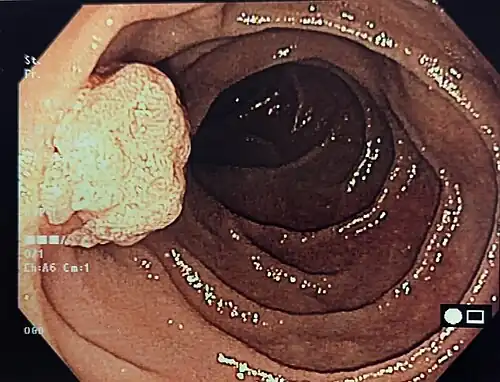

Viele Papillentumoren werden zufällig bei Magendarmspiegelungen entdeckt. Andere verursachen durch Verengung der Papille Gallestauungen oder eine obstruktive Pankreatitis (Entzündung der Bauchspeicheldrüse) mit den entsprechenden Symptomen wie Bauchschmerzen, Übelkeit und Gelbsucht. Bösartige Tumoren ab einer gewissen Größe können Blutarmut, Schwäche und Gewichtsverlust bedingen. Im Blut sind die für Lebererkrankungen typischen Enzyme, das Bilirubin, die Pankreasenzyme Lipase und Amylase sowie meistens auch die allgemeinen Entzündungsparameter erhöht. Der Nachweis ist mit einer Endoskopie leicht möglich. Weiterführende Methoden sind ERCP, Ultraschall (auch endoskopischer Ultraschall), Computertomographie oder Kernspintomographie. Ob ein Tumor gut- oder bösartig ist, entscheidet sich endgültig erst nach dessen vollständiger Entfernung und mikroskopischer Aufarbeitung durch den Pathologen.

Sehr kleine, glatte Papillentumoren, die weder bluten noch Verhärtungen aufweisen, können als gutartig eingestuft und nur beobachtet werden. Alle anderen Tumoren müssen entfernt werden. Mit dem Endoskop ist das bei gutartigen, nicht zu großen Tumoren möglich, wenn sie nicht zu tief in die Papille eingewachsen sind; andere Befunde (>4–6 cm oder in die Tiefe wachsend) erfordern einen operativen Eingriff, der unter Vollnarkose in einem Krankenhaus durchgeführt wird. Bösartige Tumoren müssen mit Sicherheitsabstand entfernt werden, was in der Regel eine Teilentfernung der Bauchspeicheldrüse und der umgebenden Lymphknoten bedeutet. Ist die Einordnung unsicher, kann zunächst endoskopisch eine Gewebeprobe entnommen und abhängig vom Ergebnis der eigentliche Eingriff geplant werden. Chemotherapie und Strahlentherapie werden nur im Einzelfall eingesetzt. Eine Leitlinie ist für diese seltene Tumorart bisher nicht entwickelt worden.